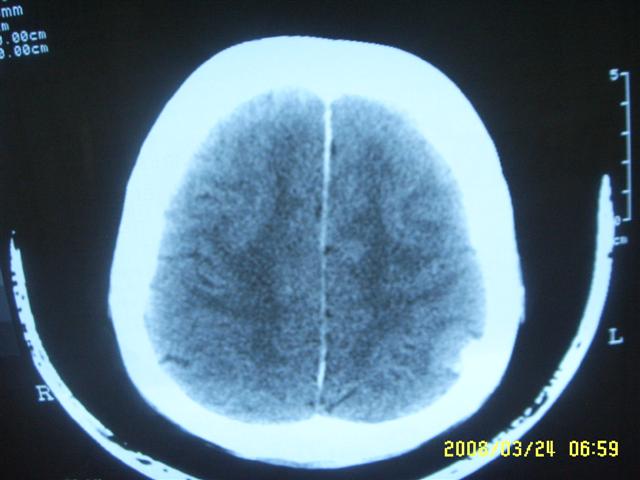

以下是引用dyqct在2008-4-2 20:09:00的发言:[br]考虑为:神经纤维瘤病(nf1型)。建议增强进一步检查。